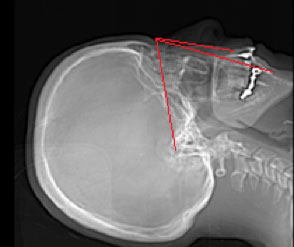

Tomografia computada Vies Aèries amb mesures cefalomètriques

S'utilitza per a l'estudi de les vies aèries superiors en pacients amb ronquera o apnea de la son. Ens permet valorar l'àrea de diferents aeri i mida de l'úvula.

Exemples